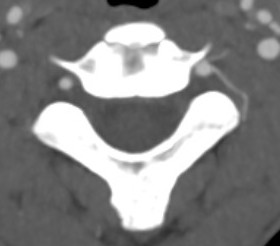

Anatomy

Origin from subclavian arteries

- anterior to C7 transverse process

- enter at C6 and travel in transverse foramina

Stay medial to uncovertebral joints